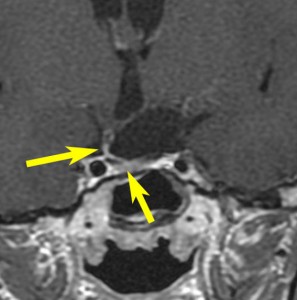

鞍隔膜下 infradiaphragmic type

7歳の子が視力障害で発症しました。両耳側半盲という症状です。典型的な鞍隔膜下頭蓋咽頭腫です。ガドリニウム造影剤を入れないMRIでみえる,黄色い矢印の先の白い高信号は抗利尿ホルモンです。ですから下垂体機能もまだ残っていて,尿崩症はありません。視力障害が戻らないことがあるのでなるべく早く,経鼻的な手術で摘出した方がいいものです,簡単 o(^-^)o